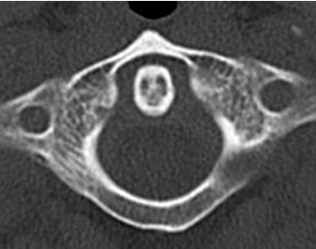

Normalmente el espacio atlantoaxial en la proyección lateral, es menor de 6 mm en los niños y de 3 mm en los adultos. (7). (Fig 191, 192 y 193).

Fig 191. Odontoides normal.

Rx lateral. Espacio atlantoaxial normal. Menor de 6 mm en niños y de 3 mm en adultos.

Fig 192. Odontoides normal.

TAC axial. Relación normal entre la odontoides y el arco anterior de C1.